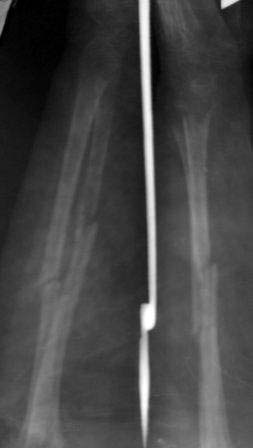

Пациентка 49 лет, по поводу перелома обеих костей предплечья оперирована в марте месяце « и/м остеосинтез спицами», через 4 месяца спицы удалены , антибиотикотерапия и фиксация гипсовой повязкой продолжена, но, учитывая что образуются ложный сустав, госпитализирована.

Повторно открывать зону перелома никак не хочется, учитывая р-картину! А что если закрыто рассверливать к/м канал ( как при БИОС), и КДО аппаратом Илизарова?

Уважаемые коллеги помогите советом! Извиняюсь за плохое качество р-снимков!